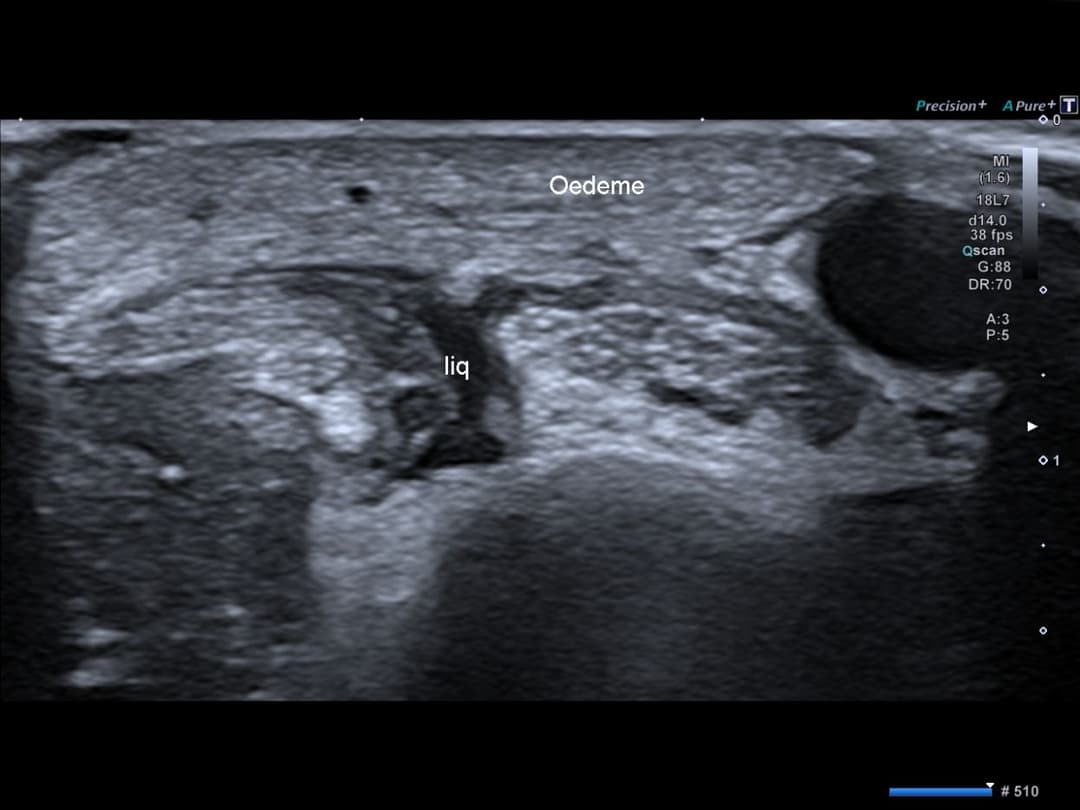

Légère lame d'épanchement dans la gaine synoviale de ces tendons en distalité de la zone conflictuelle.

Discret épanchement dans la gaine synoviale